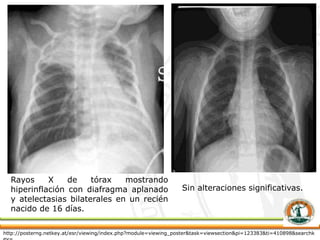

 Radiografía de tórax

Rayos X de tórax mostrando

hiperinflación con diafragma aplanado

y atelectasias bilaterales en un recién

nacido de 16 días.

Sin alteraciones significativas.